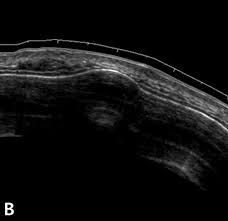

Ультразвуковое исследование не является базовым методом для диагностики остеомы, потому что позволяет оценить только поверхностные и прилежащие к коже костные образования, не обеспечивая полноценной оценки плотной костной структуры и глубоко расположенных образований. Косвенно УЗИ выявляет следующие анатомические признаки:

В серошкальном режиме визуализируется гиперэхогенное образование с акустической тенью, соответствующее участку плотной кости.

Определяется ровная, чётко очерченная граница между остеомой и мягкими тканями, что позволяет уточнить наружную локализацию.

В режиме цветового допплера кровоток внутри остеомы отсутствует, однако может наблюдаться реактивное усиление сосудистого рисунка в окружающих тканях.

Фиксируется смещение смежных структур, если остеома оказывает давление на мышцы или сосуды в поверхностных зонах.

При пальпации с одновременной ультразвуковой визуализацией подтверждается отсутствие подвижности образования и его фиксация к кости.